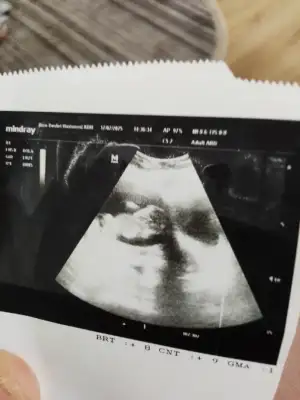

Ay bence kız10+2 karından ultrason bana da bakar mısınız lütfen aşırı merak ediyorum

Bizede bakarmisiniz10+2 karından ultrason bana da bakar mısınız lütfen aşırı merak ediyorum